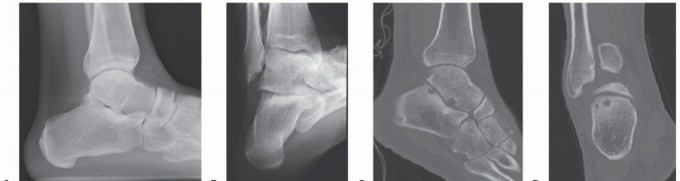

DEFINITION End-stage ankle arthritis failing to respond to nonoperative treatment ANATOMY Ankle Tibial plafon…

DEFINITION Medium-sized osteochondral defects of the talar dome May approach the talar shoulder (transition o…

DEFINITION Large osteochondral defects of the talar dome, typically involving the talar shoulder (transition …